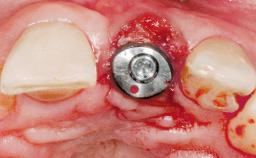

A 77-year-old male patient was referred for the management of frequent and repeated acrylic fracture of his existing mandibular fixed full-arch implant-supported metal/acrylic prosthesis. He also complained about softtissue soreness and the lack of retention and stability of his maxillary removable partial metal/acrylic prosthesis. Both prostheses had been delivered two years previously as part of his full-mouth rehabilitation (caries, tooth wear, tooth fracture). His medical history revealed high blood pressure, controlled with the use of antihypertensive medication.

# of Implants 5

Type of Implants Two-Piece

Abutment Type CAD/CAM

Prosthesis Type FDP

Retention Screw-retained, with 4 or more splinted implants Screw-retained, with 4 or more splinted implants